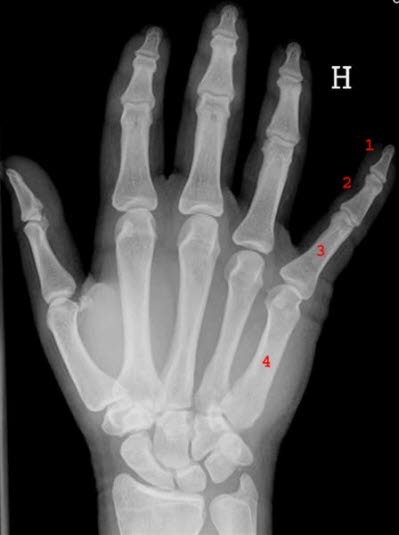

Vi finner ulike typer ledd i kroppen. Hver av ryggvirvlene kan bevege seg bare litt i forhold til nabovirvlene, men til sammen gir dette likevel nok fleksibilitet i ryggsøylen til at vi kan bøye ryggen ganske mye. Fingerleddene er hengselsledd fordi de tillater bevegelser stort sett bare i ett plan - forover og bakover. Skulderleddene og hofteleddene består av et rundt leddhode som beveger seg i forhold til en leddskål, noe som gir stor bevegelighet i mange retninger.